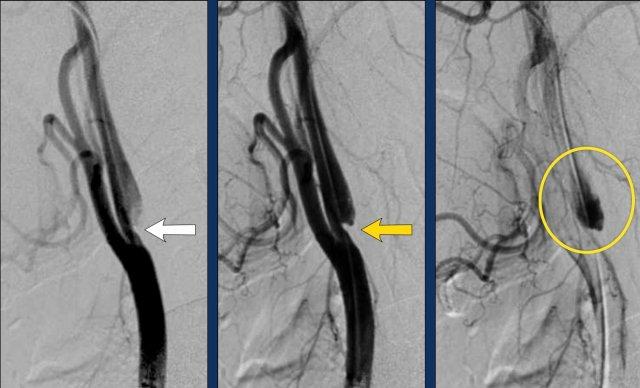

Bóc tách trên DSA

Tất cả các dấu hiệu đã thảo luận trên CTA đều tương tự và thậm chí rõ ràng hơn trên DSA.

- Catheter được đặt tại mức phình cảnh (bulbus), có hình ảnh bình thường.

Vài centimet phía trên phình cảnh, lòng mạch ICA bị lệch tâm và bị chèn ép bởi khối máu tụ thành mạch (thấy rõ hơn trên hình chi tiết số 2).

Tại mức nền sọ (đường chấm vàng), mạch máu trở về bình thường. - Hình chi tiết cho thấy thuốc cản quang đã thâm nhập vào trong khối máu tụ.

Lưu ý tổng đường kính ICA bị giãn rộng. Mũi tên chỉ lòng mạch thật sự. - Sau điều trị nội mạch, sự thông thoáng của ICA đã được phục hồi.

Khối máu tụ thành mạch phần lớn đã được tiêu huyết khối thông qua điều trị tĩnh mạch bằng chất hoạt hóa plasminogen mô tái tổ hợp (rt-PA, alteplase) trước khi can thiệp nội mạch. Vạt nội mạc (intima flap) vẫn còn nhìn thấy. Một lần nữa, bạn có thể thấy vạt nội mạc dừng lại tại mức nền sọ.